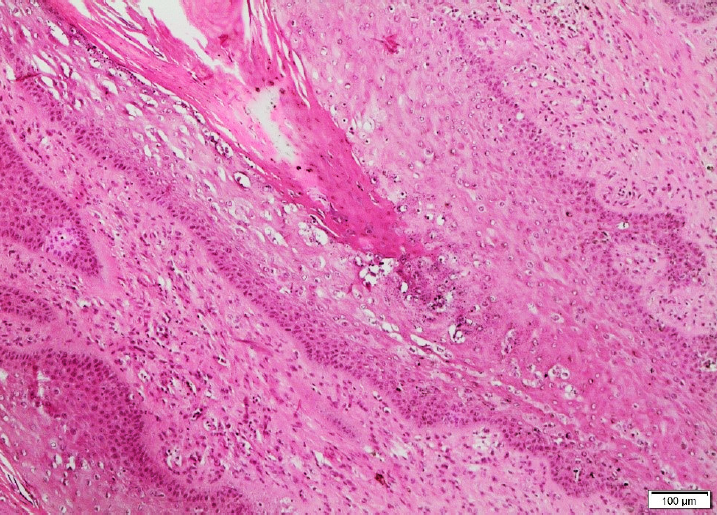

Excisional biopsy samples were taken for histopathological examination to confirm the definitive diagnosis. A blinded histopathological examination of the tissues was performed by a pathologist. After the tissue samples were fixed in 10 % neutral formaldehyde, routine tissue follow-up was performed. We took 5 μm-thick sections from paraffin blocks and stained with hematoxylin and eosin (H&E). Microscopic examination and microphotography were taken. The evaluations were done by taking into account the severity and extension of epidermal hyperplasia, acanthosis, degenerative changes, hyperkeratosis, inflammatory infiltration and vascular congestion. Thus, the diagnosis of BCP was confirmed by histopathological examination.

Histopathological examination revealed various rates of hyperkeratosis, squamous epidermal cell thickening (hyperplasia) and papillary increase of stratum spinosum layer (acanthosis) in all tissue samples. There were degenerative changes in the epidermis, especially in granular cells, ranging from diffuse spongiosis and parenchyma to severe balloon degeneration. In addition, a large number of keratohyaline granules of various sizes were observed in the cytoplasm of keratinocytes.

Numerous open cytoplasmic vacuoles and cells with irregular, eccentric and hyperchromatic nuclei were noted in the stratum granulosum and spinosum layers. Significantly increased connective tissue (fibroblasts) was observed in the dermis as nested bundles and there were islets consisting of stratum spinosum cells between these enlarged connective tissue cells. In the dermis, hemorrhage and vascular hyperemia, mononuclear inflammatory cell infiltration that mostly consisted of lymphocytes, were observed.

The severe proliferation of connective tissue in the dermis was observed in some cases. Papillomatosis was confirmed by histopathological examination in all cases. In addition, 18 (75 %) of these masses were in characteristics of papillomas and 6 (25 %) of fibropapillomas. Three examples of histopathological images are presented in Figures 3, 4, and 5.